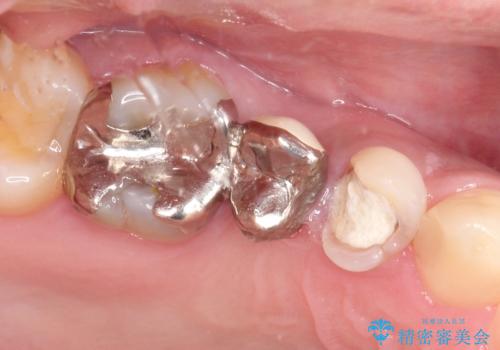

右上のブリッジが途中で切断されて、手前の歯が根の治療の途中でした。

以前は保険治療で作られた金属のブリッジを装着されていましたが、オールセラミックブリッジを装着することにより、審美的にも改善されました。